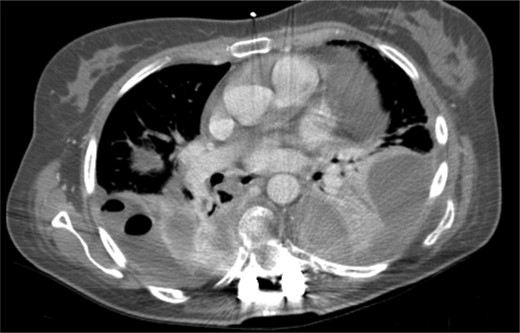

The patient started the pulmonary rehabilitation protocol by the second postoperative day, showing encouraging progression. However, by the third day, she initiated complaints of progressive dyspnea with associated impaired gas exchange. A CT scan confirmed bilateral hemothorax requiring bilateral thoracentesis (Fig. 4), after which she immediately recovered from the previous symptoms.

It was only by the 19th postoperative day, which the patient showed worsening of her general status with fever, dyspnea, decreased gas exchange and an increase in inflammatory markers. A new CT scan was performed, revealing a moderate fluid collection in both lungs, compatible with empyema (Fig. 5). The patient evolved to a septic state, which required her to be transferred to the intensive care unit.

Postoperative thoracic CT scan; large septated empyema, extending from the surgical site to both pleural cavities, was found to be the cause of deterioration of the patient's general condition.